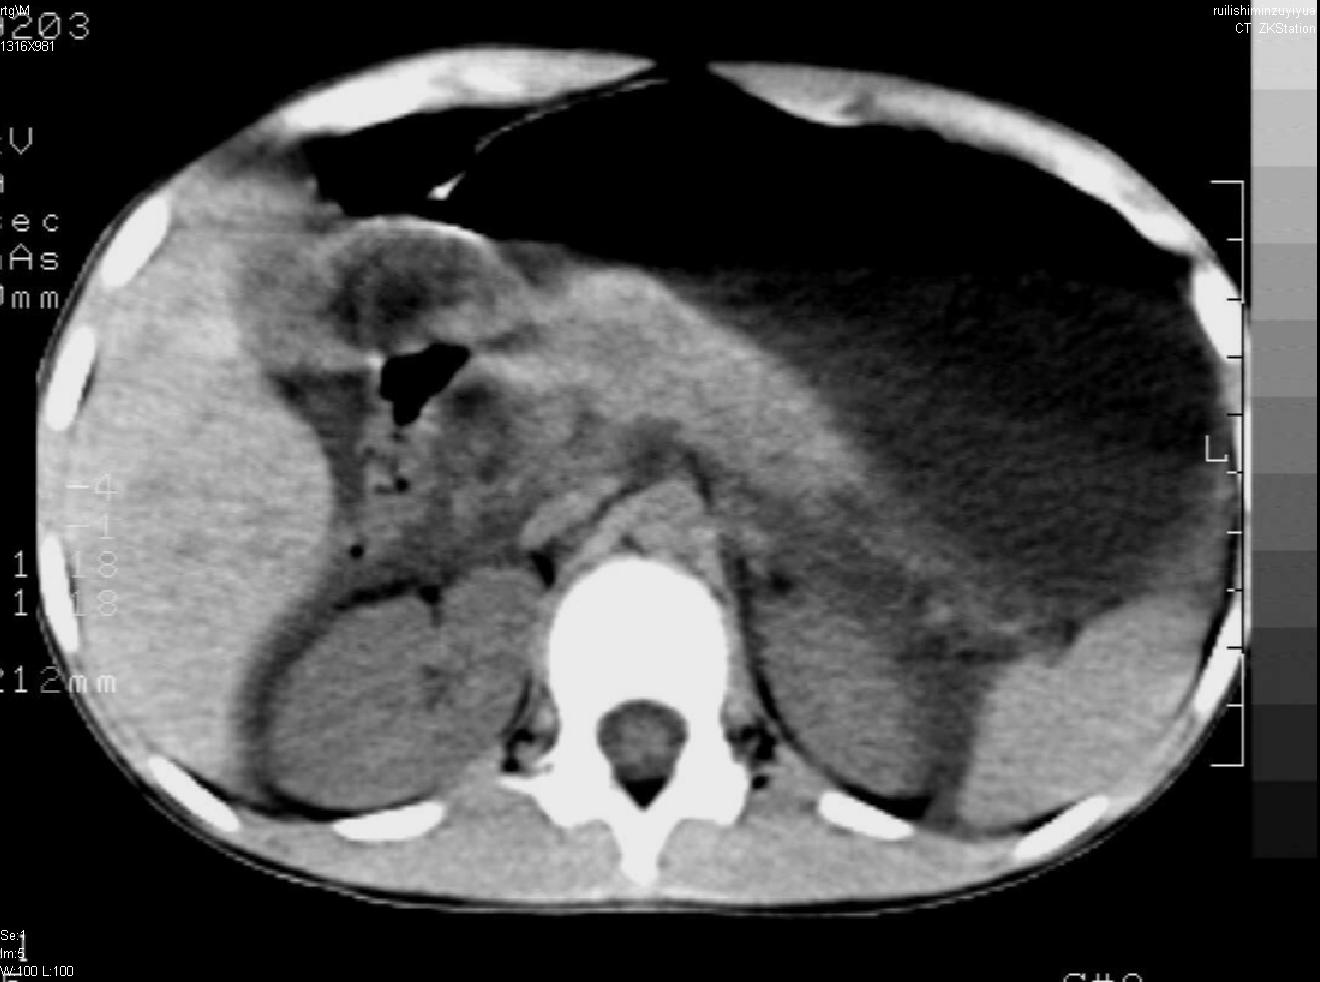

标题: PED0282:女,10岁,上腹疼痛2周 [打印本页]

标题: PED0282:女,10岁,上腹疼痛2周

b超:胆囊结石。疑坏死性胰腺炎

支持小儿急性坏死性胰腺炎。

支持急性胰腺炎并腹膜炎。

急性胰腺炎,腹腔积液